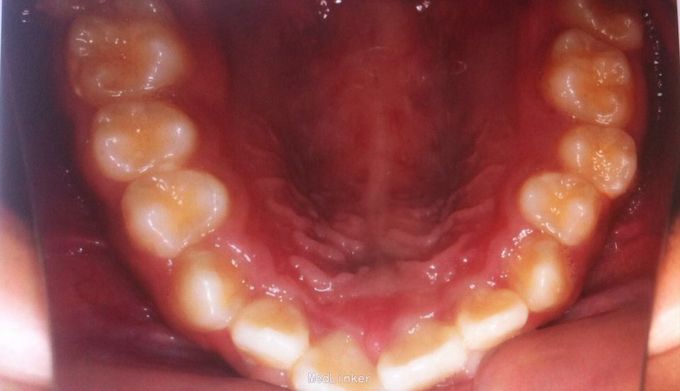

恒牙期 25正锁合 磨牙中性关系 前牙一度深覆盖深覆合 牙列拥挤 张口型异常

安氏一类 不拔牙矫治,直丝弓矫治器,排齐整平上下牙列,治疗后前牙覆合覆盖正常,磨牙中性关系,维持现有面型